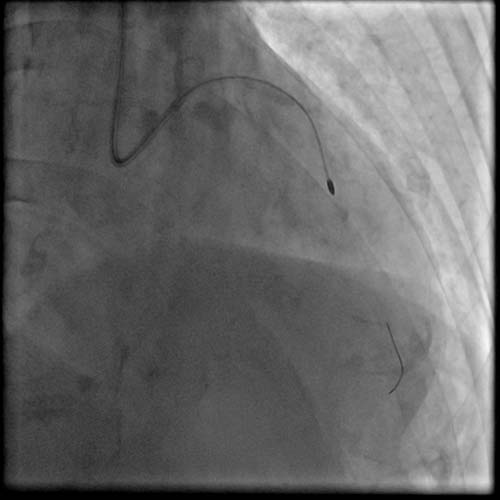

术前,苑海涛主任带领团队成员共同讨论制定手术方案,结合患者冠脉造影结果,拟对前降支钙化病变进行冠脉旋磨术及支架置入术。

患者高龄,冠脉钙化严重,使得手术难度大、风险高,对操作者的技术及经验提出了更高要求。经过苑海涛主任大胆细致的旋磨治疗,前降支病变顺利开通并成功植入支架。术后,患者胸痛等症状明显缓解,顺利出院。

苑海涛主任介绍,钙化病变是所有介入医生都感到头痛的“硬骨头”,对付如石头般坚硬的斑块,常规的球囊、支架扩张技术难以充分扩张病变。而冠状动脉旋磨术则是处理钙化病变的有效手段,通过高速旋转带有金刚石颗粒的旋磨头对斑块进行研磨销蚀,在血管内开“隧道”,以此解决冠脉介入治疗。冠脉内旋磨术操作难度大、风险高,要求介入医生和团队必须有高超的技艺和默契的配合,尤其是年龄超过70岁的患者,脏器功能更差,冠脉旋磨对术者的心理能力和技术水平都是极大的考验。